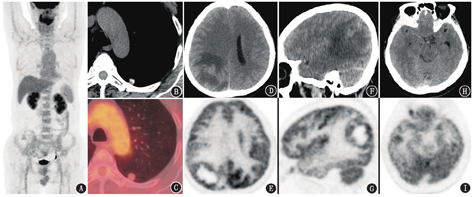

病例2 患者男,60岁,2周前无明显诱因出现走路偏斜,曾因此于行走中头部撞到大树后出现头晕、恶心,当地医院脑MRI见右侧颞叶、顶叶及右侧脑膜多发异常信号,增强后明显强化,周边大片水肿带,不除外脑转移瘤。行胸部CT发现左肺下叶背段结节(直径1.1 cm)。为进一步明确病变性质及分期,患者行18F-FDG PET/CT显像(图2)。脑PET/CT显像可见右侧顶枕叶囊性占位,大小为4.4 cm×3.2 cm,中心囊腔呈放射性缺损区,囊壁厚薄不均,代谢与相邻皮质相近,SUVmax为12.1,周围伴大片状低密度水肿带;右侧颞叶亦可见代谢摄取增高小结节,大小为1.0 cm×0.7 cm,SUVmax为10.1;右侧丘脑后部条片状代谢增高影,SUVmax为6.8;邻近右侧大脑皮质、基底节及左侧小脑代谢减低,中线结构向左移位。左肺下叶背段胸膜下可见一实性结节,大小1.2 cm×1.1 cm,边缘尚光整,伴钙化,代谢与纵隔血池相近,SUVmax为1.4。

病例2中脑占位为多发,其中较大病灶与病例1相似,伴囊变、代谢高、周围水肿明显,仍应先除外脑转移瘤的可能。那么病例2中的肺结节是否可能为原发灶?该结节为周围性的实性小结节,没有明显分叶征、毛刺征、胸膜牵拉征等周围型肺癌的表现,代谢不高于纵隔血池,纵隔窗还可见结节有明显钙化。黏液腺癌和典型类癌外形可较规整,代谢活性也不太高,前者是由于肿瘤细胞成分少、黏液含量多而在PET表现为较低程度的代谢活性,而黏液成分有时可表现为高于软组织的密度或伴小钙化灶。本例的钙化范围相对于瘤体来说较大,密度高,在肿瘤中比较少见。肺类癌则是由于肿瘤细胞分化良好、恶性程度低,FDG代谢通常不高,一般发病年龄偏年轻,多为中央型,表现为支气管腔内的类圆形或圆形结节,管腔内病变通常只占病变的一小部分,形成"冰山征",增强扫描明显强化,本例不考虑。本例的肺结节从形态、密度、代谢来看更像良性病变,如肺错构瘤。

若肺结节不是原发灶,那么就不支持脑转移瘤的诊断。虽然颅内多发病灶相对来说更常见于脑转移瘤,但胶质瘤、淋巴瘤、脑脓肿等也会多发。脑淋巴瘤可能来源于血管周围未分化的多能细胞,肿瘤细胞在血管周围间隙内浸润生长,肿瘤可单发也可多发,多位于脑内靠近表面或中线的部位,好发于基底节、胼胝体、丘脑和脑室周围,肿瘤一般密度比较均匀,无明显包膜,出血、囊变少见,周围水肿程度低于转移瘤或高级别胶质瘤;另外,由于原发的脑淋巴瘤多为弥漫性大B细胞淋巴瘤,FDG代谢一般明显增高。这些特点与本例表现不符。脑脓肿患者通常有寒战、发热、血象升高等感染征象,本例也不考虑。因此,本例颅内病变鉴别的重点是脑转移瘤和胶质瘤。

若为胶质瘤,病灶多发、水肿坏死明显、代谢增高,则应为高级别胶质瘤。脑转移瘤和胶质瘤18F-FDG PET/CT表现有诸多的相似之处,如均可分布于皮质下,可出现液化坏死,瘤周水肿明显,肿瘤有不同程度代谢增高。这些相似的表现为鉴别诊断带来一定困难,这时就体现出PET/CT对全身病变探测的优势,如果有明确的原发灶,则考虑脑转移瘤,若没有原发灶,则胶质瘤可能性更大。

再来看颅内病变本身的特点。一般来说,脑转移瘤的瘤周水肿更为显著,不成比例的小结节大水肿有利于脑转移瘤的诊断;此外环形病灶的环外壁在脑转移瘤相对规则,而胶质瘤环壁一般厚薄不均,环外壁毛糙不规则,形如"花环"状;脑转移瘤FDG代谢通常高于脑白质,而WHO Ⅰ~Ⅱ级胶质瘤FDG代谢多低于白质或与白质相当[1]。病例2最显著的右侧顶枕叶囊性占位,囊壁厚薄不均,外缘不规则,呈"花环"壁结节状代谢增高,加之PET/CT全身显像其余部位没有明显原发恶性肿瘤征象,脑内病变要首先考虑高级别胶质瘤。之后患者行右侧顶枕叶占位手术切除,术后病理:高级别胶质瘤,伴大片坏死,结合形态及免疫组织化学检查,考虑为间变少突胶质细胞瘤或胶质母细胞瘤。免疫组织化学检查结果:CD34(血管+),广谱细胞角蛋白(AE1/AE3;-),上皮细胞膜抗原(epithelial membrane antigen, EMA;-),少突胶质细胞转录因子-2(Oligo-2;+),胶质纤维酸性蛋白(glial fibrillary acidic protein, GFAP;+),神经元核抗原(neuronal nuclei antigen, NeuN;散在+),P53(散在+),S100蛋白(+),突触素(synaptophysin, Syn;部分+),异柠檬酸脱氢酶1(isocitrate dehydrogenase 1, IDH1;+),X连锁α地中海贫血/精神发育迟滞综合征蛋白(X-linked α-thalassemia retardation syndrome protein, ATRX;+),细胞增殖核抗原Ki-67(40%)。